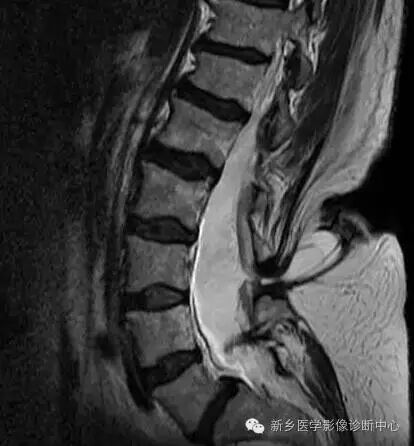

脊柱MRI提示椎管内占位及相应水平椎体后缘扇贝样压迹(白箭)